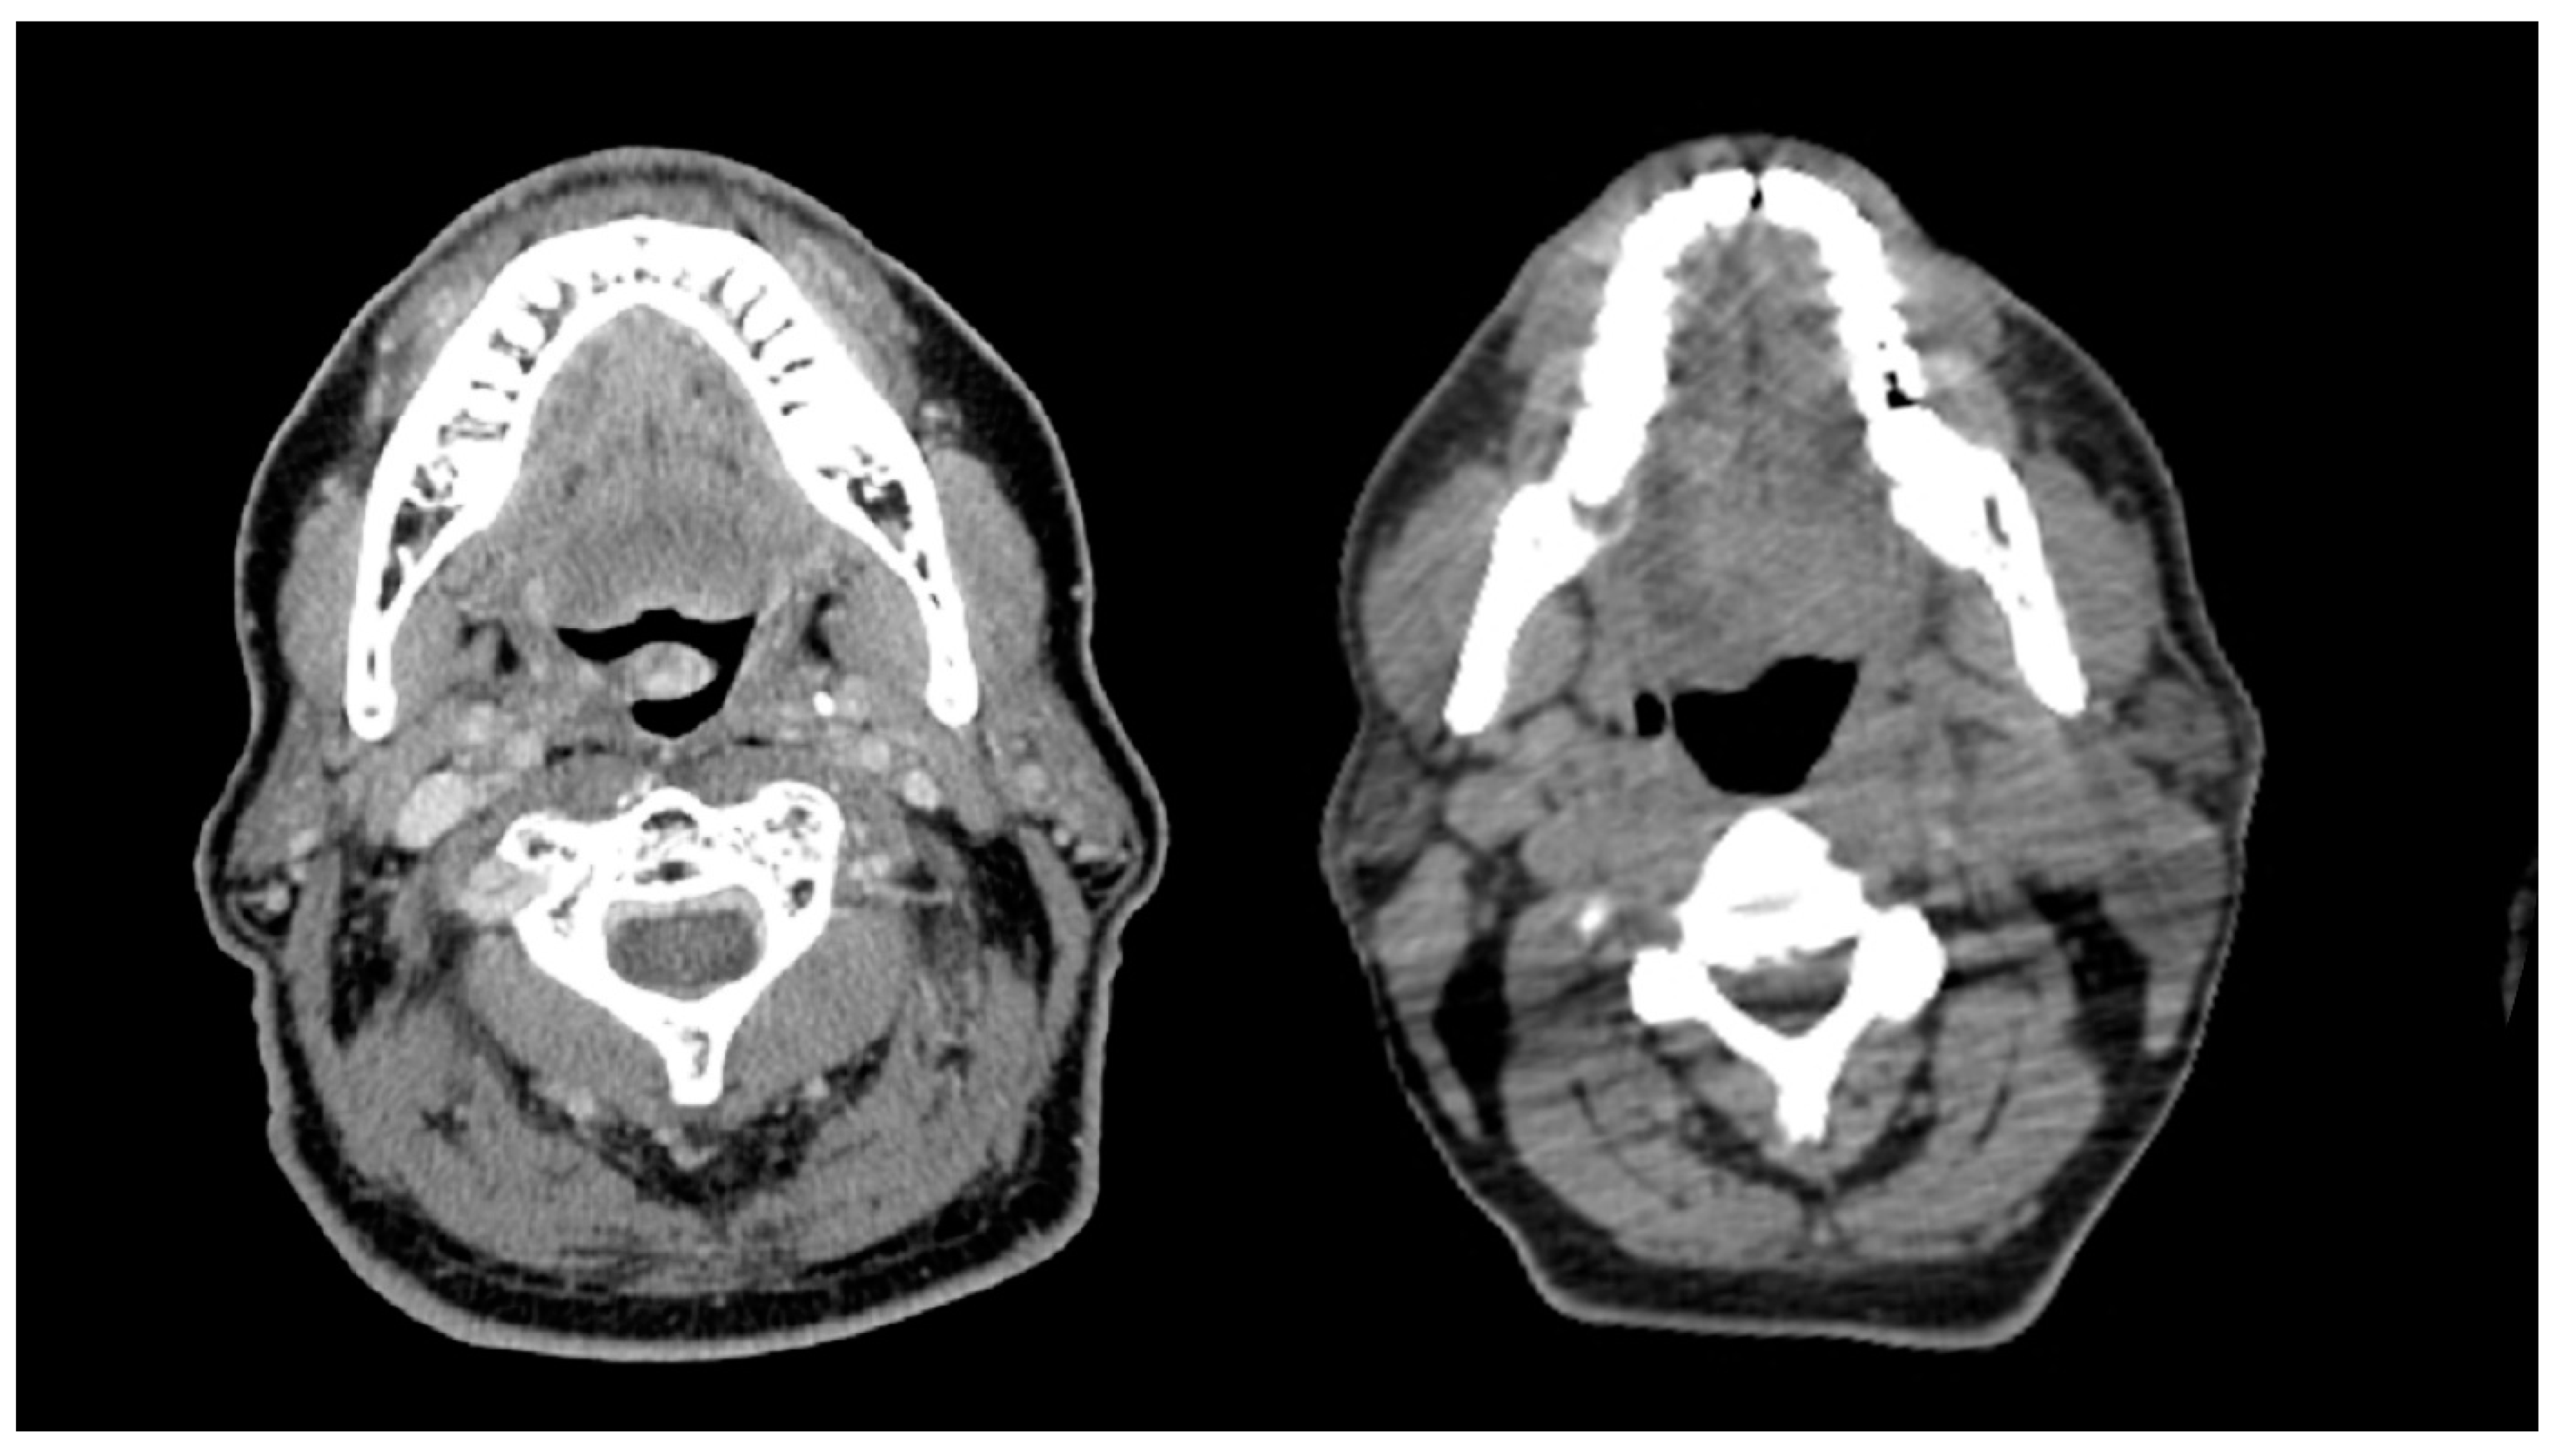

Thirty-four percent of patients experienced at least one missed radiation day due to toxicity, with a median of two treatments missed (range, 1–30). On UVA, Older patients required more radiation treatment breaks compared to younger patients (51.0% versus 29.9%, p < 0.01) (Table S1). MVA to identify factors associated with at least one radiation treatment break (Table 2) found only age ≥70 as a predictor (p = 0.012). Twelve percent of patients required a prolonged radiation treatment break, defined as a break of 1 week or greater. The most common reason for prolonged break was CTCAE grade 3 mucositis (36.3%). Older patients were more likely to require prolonged treatment breaks than younger patients on UVA (27.5% versus 8.6%, p < 0.01) (Table S1). On MVA (Table 2), age ≥70 (p < 0.01), low albumin status (p = 0.03), and sarcopenia (p = 0.04) were identified as predictors of prolonged radiation treatment breaks. Representative CT slices comparing radiation toxicity of an older adult with sarcopenia and younger adult without sarcopenia are shown in Figure 2. Nutritional dependence on PEG tube (CTCAE grade 3) was similar between groups (65.6% younger versus 66.7% older, p = 0.89). One-hundred six patients lost greater than 10% of their pretreatment body weight (42.5% younger versus 23.5% older patients, p = 0.012). Patients requiring hospital admission (CTCAE grade 3) during treatment occurred in 68 total patients (25.0%), with a trend toward older patients (35.3% versus 22.6%, p = 0.060).

Figure 2. A comparison of older and younger patients with and without sarcopenia with similar BMI. The left panel represents a 70-year-old man with HPV-positive oropharynx cancer with sarcopenia (BMI 27.6 kg/m²) experiencing 10 days of radiation treatment delay, while the right panel represents a 56-year-old man with HPV-positive oropharynx cancer without sarcopenia (BMI 26.7 kg/m²) having no days of radiation treatment delay.